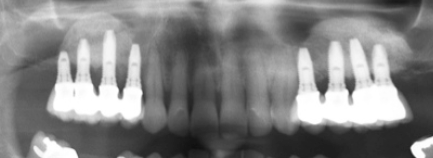

Sinus lift à la prothèse

Comment rendre un cas complexe en un cas simple ?

Toutes les étapes du Sinus lift à la prothèse.